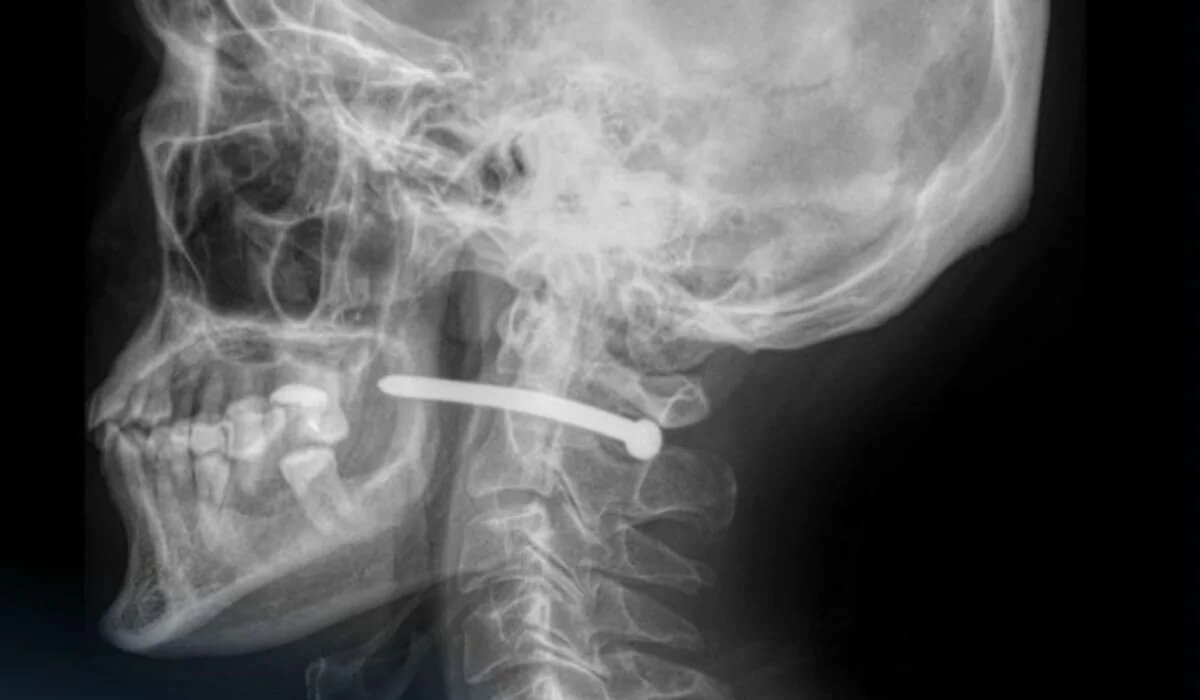

Во время ремонта 51-летний житель Петропавловска получил опасную травму: гвоздь из пневматического пистолета пробил кожу за ухом и остановился всего в нескольких миллиметрах от позвоночника, передает Azattyq Rýhy со ссылкой на Петропавловск.news.

После рентген-исследования врачи установили, что гвоздь прошёл рядом с шейным отделом позвоночника. Медики отметили, что пострадавшему чудом повезло – жизненно важные структуры не были задеты.

«Челюстно-лицевыми хирургами проведено удаление инородного тела, ревизия и обработка раны. После наложения швов и стерильной повязки пациент с рекомендациями отпущен домой», – сообщили в больнице.